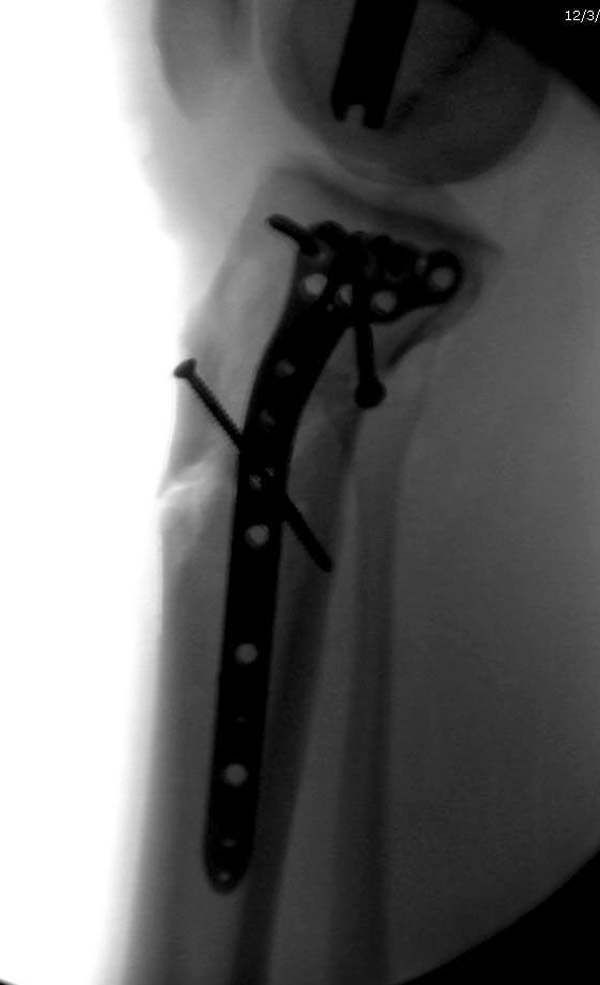

здравствуйте! создается впечатление о фиксации перелома голени в варусном положении

Согласен, на снимке “создается впечатление о фиксации перелома голени в варусном положении”, но на других отсутствует..

LCP по медиальной поверхности+артроскопический контроль суставной площадки